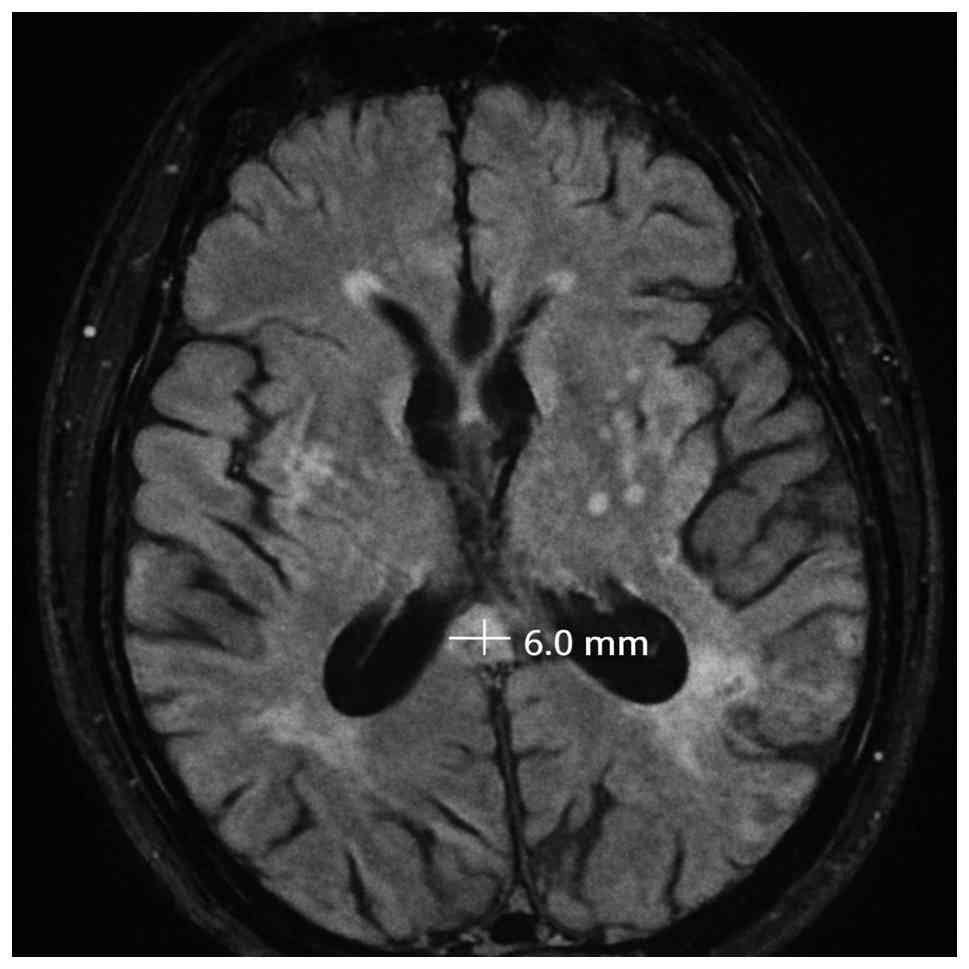

Measurement of splenial FLAIR hyperintensity

Splenial FLAIR hyperintensity thickness was measured in the anteroposterior direction on the axial FLAIR slice where the hyperintensity appeared most prominent, using the outer margins of the hyperintense area as anatomical reference points; a sample case is presented in Fig. 2. Two independent observers (one with 2 years and another with 10 years of neuroradiology experience) performed the measurements in a blinded manner to minimize bias. The interobserver agreement was assessed using the intraclass correlation coefficient (ICC).

Anteroposterior thickness of splenium

hyperintensity.

Figure 2

Anteroposterior thickness of splenium hyperintensity.